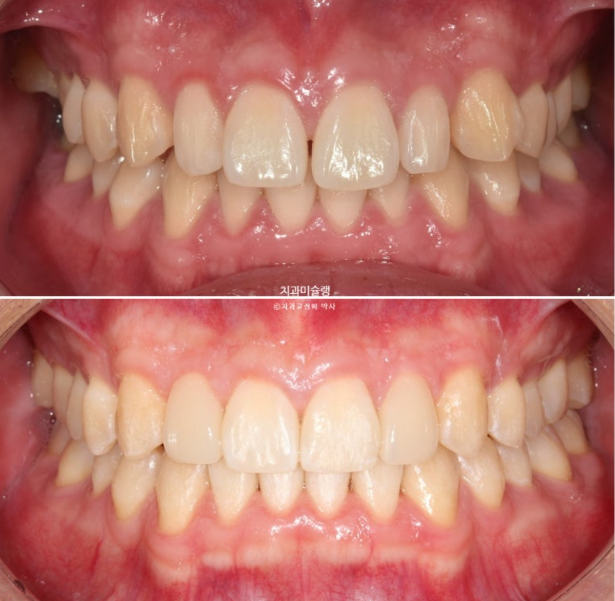

이제 왜소치 무삭제 라미네이트가 들어갈 차례 입니다.

왜소치 라미네이트는 주변치아 색깔에 어울리도록 맞추는 것이 좋습니다.

자연스럽게 잘 치료가 되었습니다.

거미스마일과 중심선이 개선이 되었습니다.

깔끔하고 정돈된 미소가 돋보입니다.